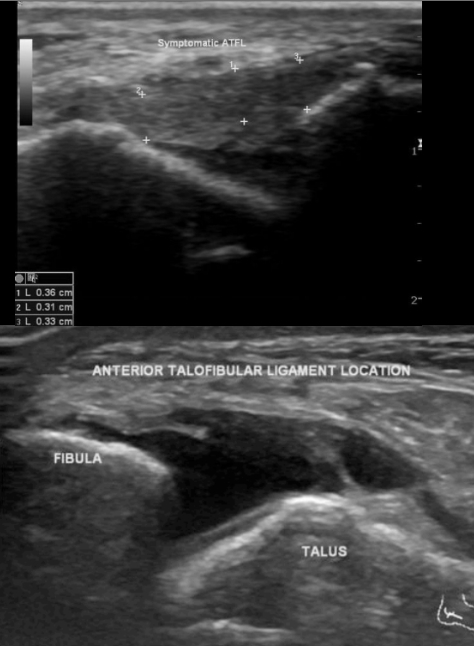

22

Para qué se usa el US en un esguince de tobillo?

• Utilidad limitada

• permite ver el ligamento talofibular anterior (ATFL)